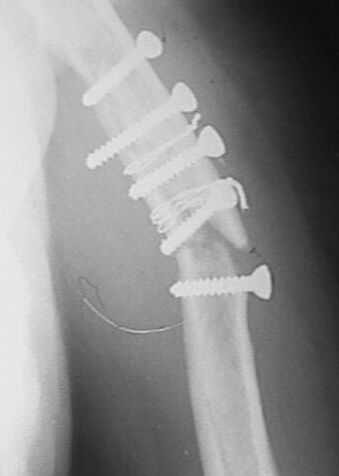

Больная 45 лет оперирована в июле 2002 г, иммобилизация в течение 3 месяцев. После операции были явления неврита лучевого нерва, которые в последующем исчезли. Во время проведения ЛФК отмечается появление болей, патологическая подвижность в месте перелома, деформация плеча.

ККК>Считаю неграмотным вкручивание винтов с конусными или закругленными

головками, так как они вклиниваясь в кость, раскалывают ее

Подобное межфрагментарная фиксация описана и рекомендована группой АО (Швейцария ).

Привожу рисунок из руководства по внутреннему остеосинтезу.tmpB 201-6

В том , что остеосинтез проведен с грубыми нарушениями техники фиксации, которые привели к плохому сращению перелома согласен.

На мой взгляд, в данном случае, перелом сросся скорее не благодаря, а вопреки "лечению".

Считаю неграмотным вкручивание винтов с конусными или закругленными головками, так как они вклиниваясь в кость, раскалывают ее. Два крайних винта на представленных снимках захватили только по одному из отломков. О

серкляже и говорить не хочется: циркулярно жгутирует кость, зачастую удаление проволоки травматичнее ее установки и т.д. За двадцать лет работы ни разу не наладывал торакобрахиальную гипсовую повязку т.к. считаю ее издевательством над пациентом. При таких грубых нарушениях современных принципов травматологии странно слушать вопросы о препаратах, стимулирующих сращение. За деньги, которые потрачены на приобретение таких дорогих препаратов как миакальцик, Са Д3, остеогенон, Вы могли бы приобрести нормальные металлоконструкции для полноценного остеосинтеза и запасную дрель.